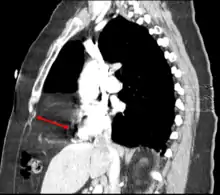

Congenital diaphragmatic hernia (CDH) is a birth defect of the diaphragm. The most common type of CDH is a Bochdalek hernia; other types include Morgagni hernia, diaphragm eventration and central tendon defects of the diaphragm. Malformation of the diaphragm allows the abdominal organs to push into the chest cavity, hindering proper lung formation.

This rare anterior defect of the diaphragm is variably referred to as a Morgagni, retrosternal, or parasternal hernia. Accounting for approximately 2% of all CDH cases, it is characterized by herniation through the foramina of Morgagni which are located immediately adjacent and posterior to the xiphoid process of the sternum.[4]